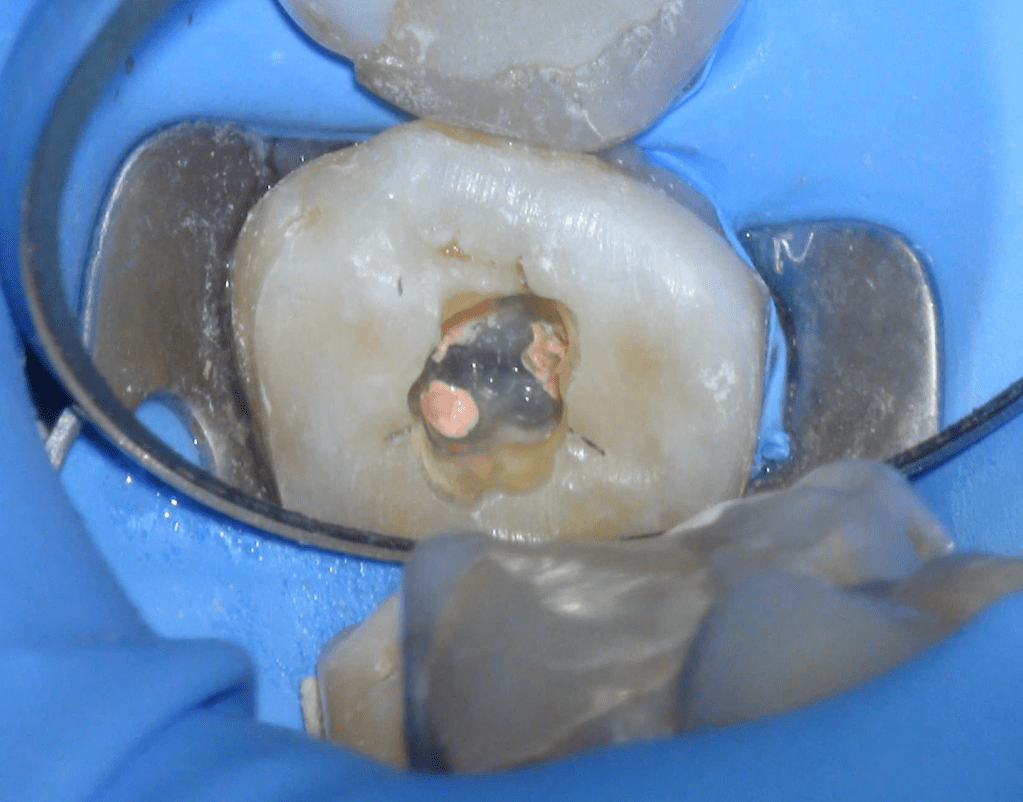

Pulpotomía biodentine + reco preendio